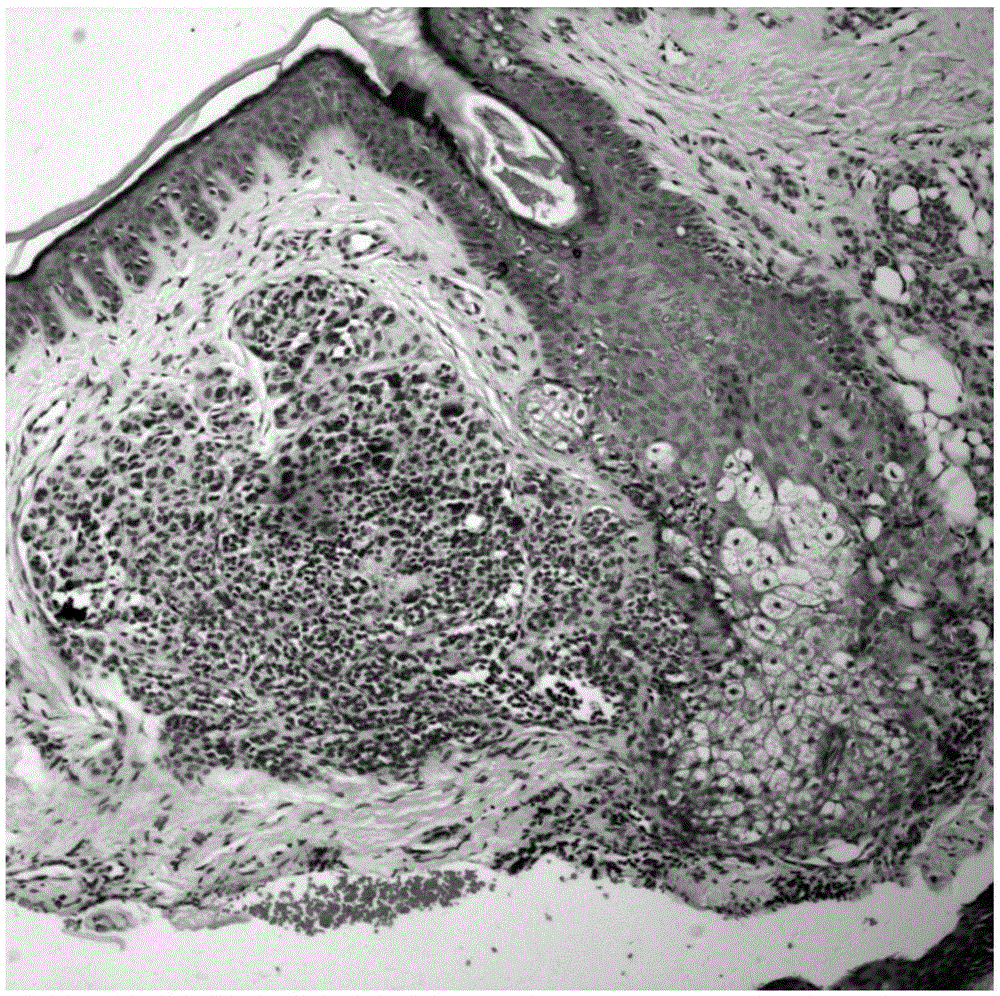

基于深度学习的皮肤活检图像病理特性识别方法